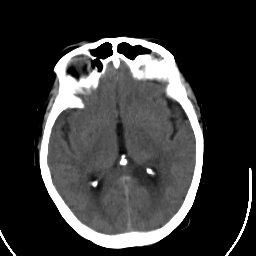

Stroke CT #2 -- Slice #12

[Home][Help][Clinical] Slice 12